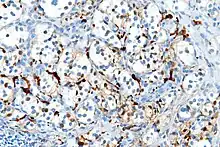

Several members of the S100 protein family are useful as markers for certain tumors and epidermal differentiation. They can be found in melanomas,[8] 100% of schwannomas, 100% of neurofibromas (weaker than schwannomas), 50% of malignant peripheral nerve sheath tumors (may be weak and/or focal), paraganglioma stromal cells, histiocytoma, and clear-cell sarcomas. Further, S100 proteins are markers for inflammatory diseases and can mediate inflammation and act as antimicrobials.[9] S100 proteins have been used in the lab as cell markers for anatomic pathology.